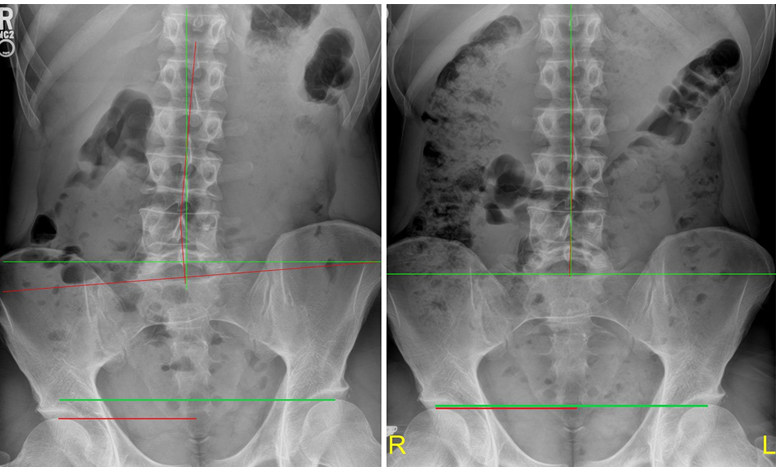

Below is a recent patient at Noracare Wellness Center with a right sided LLD measured at 16.9 mm and postural imbalance (left x-ray image). The x-ray on the right shows LLD reduction to 2.1 mm and improved postural balance using a right sided heel lift. As a result, the patients’ hip pain reduced by 80%.